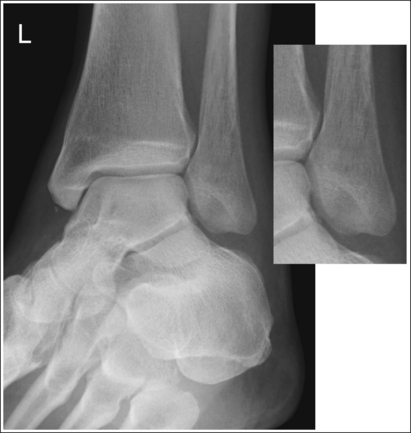

See Figures 6-49, 6-50, and 6-51 and Box 6-11.

Mortise (15 to 20 degrees oblique): The ankle demonstrates 15 to 20 degrees of obliquity. The distal fibula is demonstrated without talar superimposition, demonstrating an open lateral mortise (talofibular joint), and the lateral and medial malleoli are in profile. The fibula demonstrates slight (0.125 inch [33 mm]) tibial superimposition.

• To obtain a mortise AP oblique ankle projection with accurate positioning, place the patient in a supine AP projection with the leg extended and the foot positioned vertically (Figure 6-52). The leg and foot are then rotated the desired amount. Make certain that the foot does not invert during rotation. While viewing the plantar surface of the foot, place your index fingers on the most prominent aspects of the lateral and the medial malleoli. Rotate the patient's entire leg internally (medially) 15 to 20 degrees, until your index fingers and the malleoli are positioned at equal distances from the IR (Figure 6-53). An imaginary line drawn between the malleoli (intermalleolar plane) is then aligned parallel with the IR. This rotation moves the fibula away from the talus to demonstrate an open lateral mortise.

• Identifying poor ankle and leg rotation. If the ankle and leg are internally rotated less than the needed 15 to 20 degrees, the medial mortise will be open while the lateral mortise will be closed (see Image 36). If the ankle was internally rotated more than 15 to 20 degrees, the image will demonstrate a closed medial mortise and decreased tibial superimposition of the fibula or an open tibiofibular joint, depending on the degree of increased rotation (see Image 37).

The ankle demonstrates 45 degrees of obliquity. The lateral mortise is partially closed, the anterior and posterior cortical outlines of the lateral tibia are superimposed, visualizing the fibula without tibial superimposition, and the tarsal sinus is demonstrated. Whether or not there is an open space between the tibia and fibula on this image will depend on how closely aligned the two structures are with each other (compare the superimposition of the anterior and posterior cortical outlines of the lateral tibia and the openness of the tibiotalar joint spaces in Figures 6-50 and 6-51).

• To obtain a 45-degree AP oblique ankle projection with accurate positioning, place the patient in a supine AP projection, with the leg extended and the foot positioned vertically. The leg and foot are then internally rotated until the long axis of the foot is aligned 45 degrees with the IR (Figure 6-54).

• Identifying poor ankle and leg rotation. If the ankle and leg are internally rotated less than 45 degrees, the anterior cortical outline of the lateral tibia will be lateral to the posterior cortical outline of the lateral tibia (see Image 38). If the ankle and leg are internally rotated slightly more than 45 degrees, the anterior cortical outline of the lateral tibia will be medial to the posterior cortical outline of the lateral tibia.